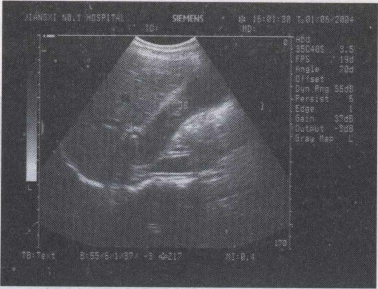

32.女,34岁,上腹疼痛不适数年,加重2天。声像图如图所示。结合超声声像图,诊断为()